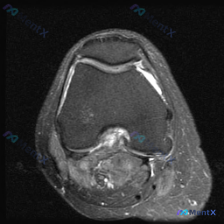

看到这例膝关节MRI,整理一下影像发现和分析思路,和大家一起讨论。 病例影像基本信息 这是一例膝关节轴位T2加权MRI图像,涵盖股骨髁间窝、髌股关节及周围软组织,具体影像发现如下: 1. 骨骼结构:股骨远端骨皮质及骨松质信号未见明显异常 2. 关节软骨:髌骨关节面软骨不均匀高信号、边缘轮廓模糊;股骨...